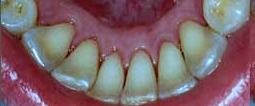

Usuwanie kamienia nazębnego , osadów – usuwanie zalegających osadów z zębów własnych lub uzupełnień protetycznych .

osad

Osady , kamień nazębny.

oczyszczone

Po oczyszczeniu